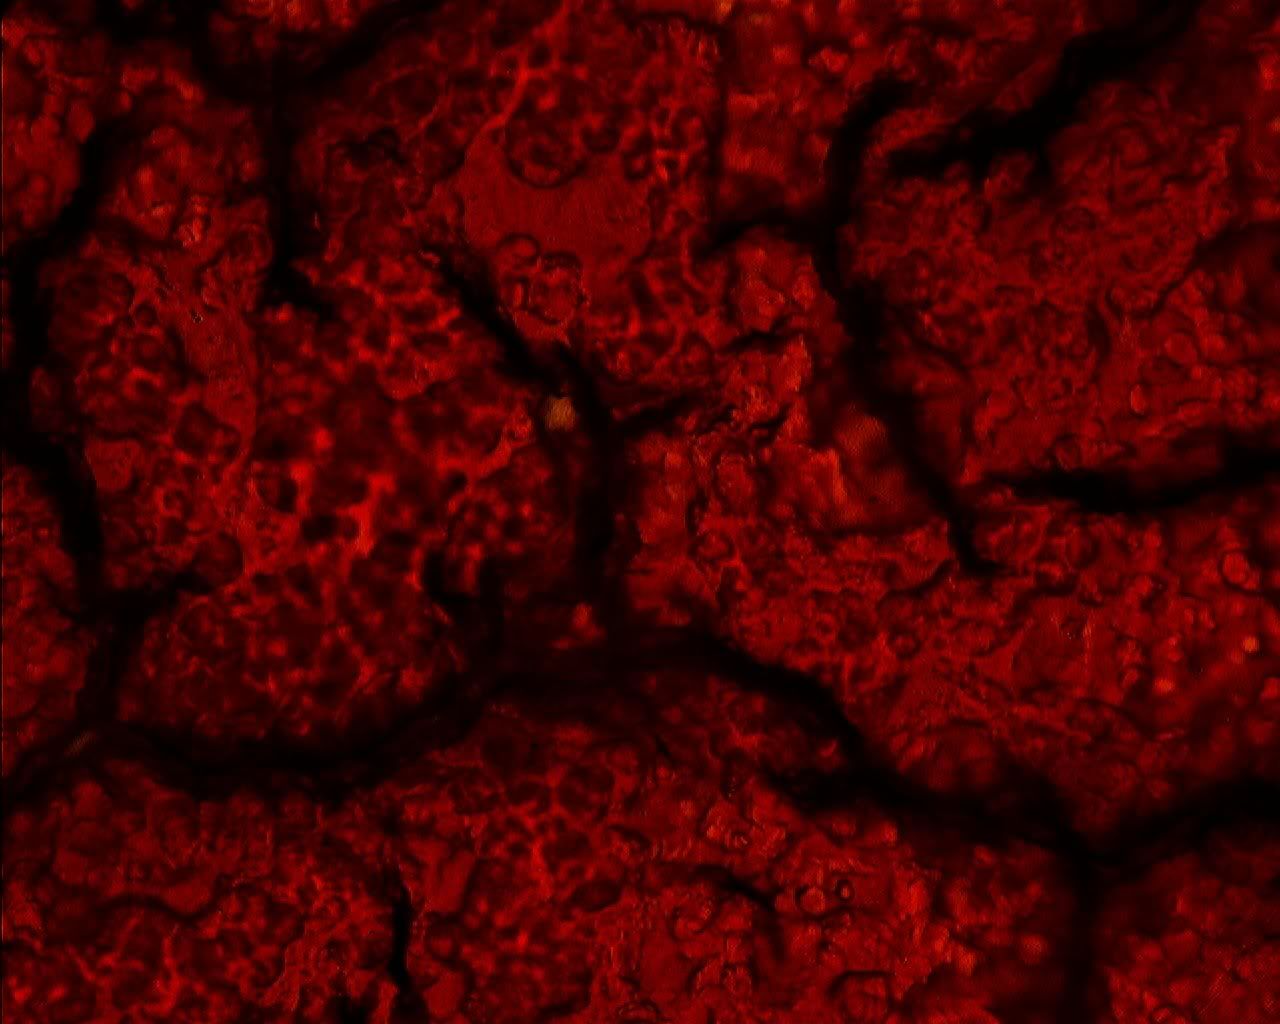

Oblique Oblate Oblique Oblate Send message Joined: 15 Aug 08 Posts: 61 Credit: 95,597 RAC: 0 |

Becky the diabetic's blood at 800x. |

Red blood cells that are not red? Doesn't make any sense to me. One would think there is a lack of iron in them. But the person they came from isn't anemic. Any ideas? |

Yep, they aren't circulating any more. Might have gone all blue blood on you. |

I havent been using my microscope lately and so havent been looking at red blood corpuscles to see how much pink is visible. Maybe the red color is so weak because one's looking through such a thin layer of protoplasm - about two microns max judging by the (7.6 micron) diameter and shape. |

You can get a special dye that will dye them red and increase contrast.... Usually a Wright's stain P.S. You can get the stain cheaper than this. This is a 1L bottle keep in mind :)   |